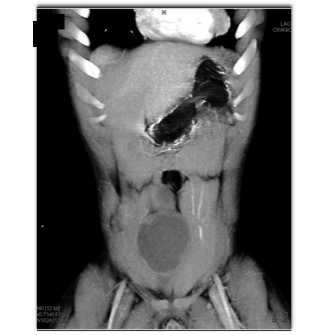

In this patient with a history Familial Polyposis (FAP) the best diagnosis is?

CTisus Quiz   CTisus Quiz

lymphoma

post op seroma

desmoid tumor

abdominal wall seroma